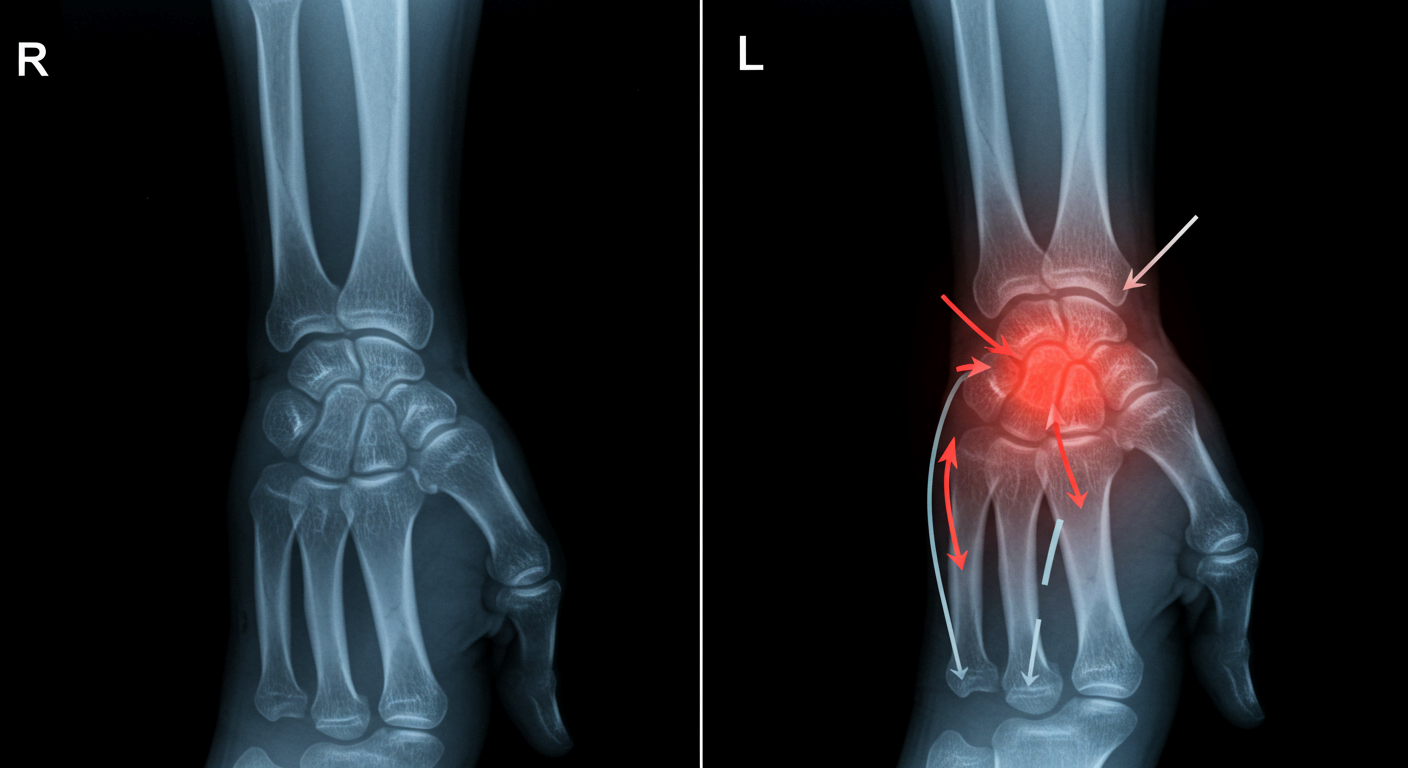

4. 손목 부상과 외상

운동 중 넘어지면서 손을 짚거나, 무거운 물건을 들다 손목이 꺾이는 등의 외상은 골절, 인대 손상, 염좌 등을 유발합니다. 부상 초기에는 단순 타박상처럼 보여도, 시간이 지나면서 통증이 지속되거나 악화될 수 있습니다.

나이가 들면서 손목 관절의 연골이 닳고 뼈끼리 부딪히면서 퇴행성 관절염이 생길 수 있습니다. 또한 류마티스 관절염처럼 면역 시스템이 손목 관절을 공격하는 질환도 통증의 원인이 될 수 있습니다.